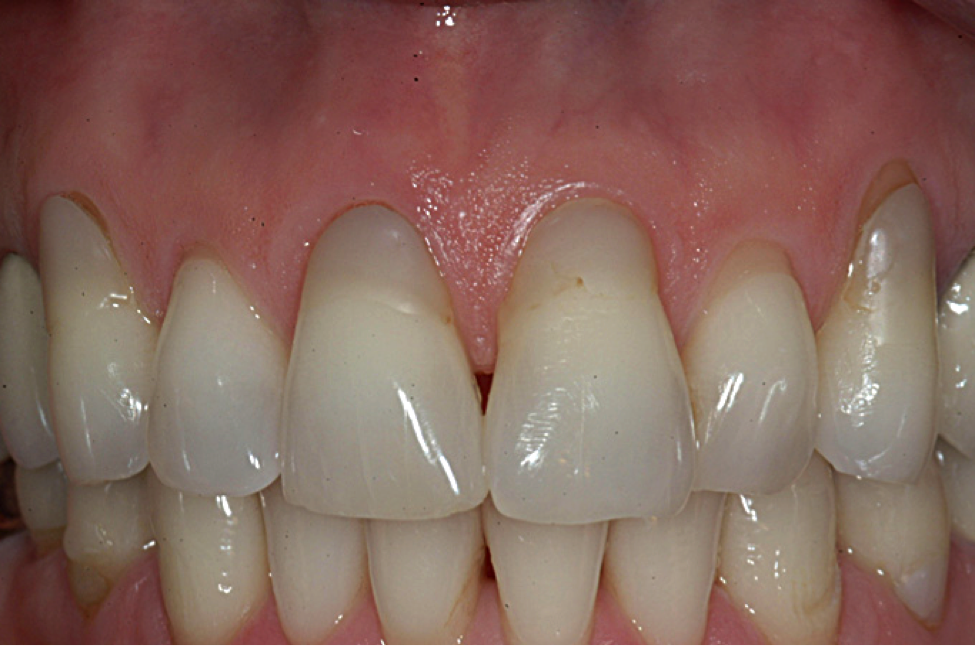

The graft was placed to the height of the original free gingival margin (FGM) (Figure 5), and no attempt was made to cover what had been the exposed root areas—the only areas covered were where biologic attachment had been previously. Interproximal sutures were used to hold the FGG in place, and a surgical dressing was applied. Figure 6 shows successful 13-year results.

Note that when FGGs fit passively onto the recipient site with complete contact on the underlining recipient bed, apical sutures are not required. However, when grafts tend to lift off the recipient site, from which the grafts obtain their blood supply, apical sutures are necessary to maintain intimate contact and fit.11,14,17